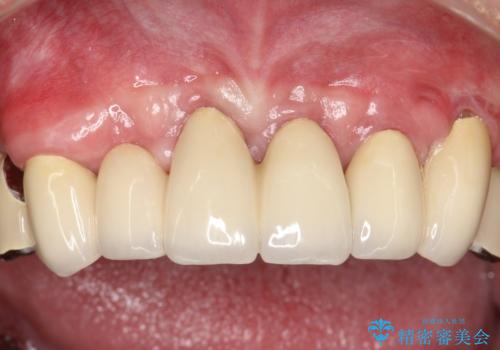

→治癒後、確定外科を行い完全に歯周ポケットを除去し、最終的に歯周補綴をおこなう

かぶせ物の種類:PFM full bake